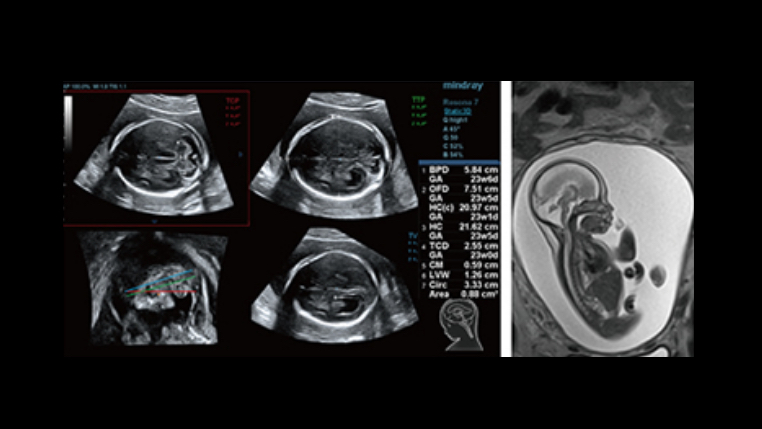

Automatic measurements of the most frequently examined parameters, including BPD, HC, FL, AC, OFD and even NT as early as 11 weeks, are available with a single click for higher productivity and reproducibility.